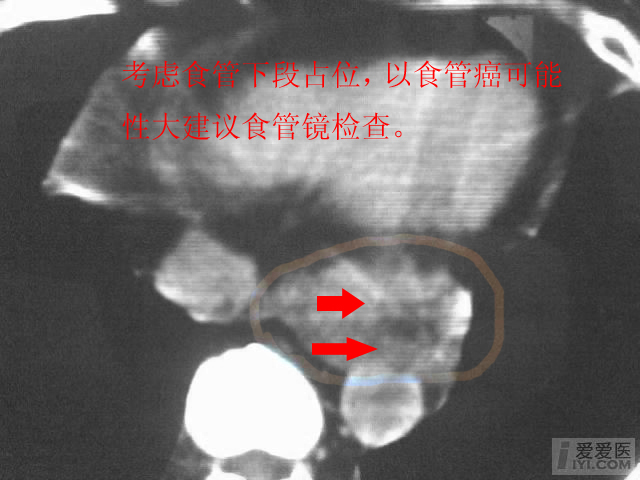

考虑食道占位,建议食道镜检

印象:食管区肿块较大,纵隔多个肿大淋巴结,多考虑食管癌转移所致

食道下段癌.

食管下段管壁增厚,周围欠清晰,考虑占位,还是做食道双对比造影或食道镜进一步检查吧!

考虑食管癌可能大。

考虑食道癌的可能,建议上消钡餐或食管镜检查